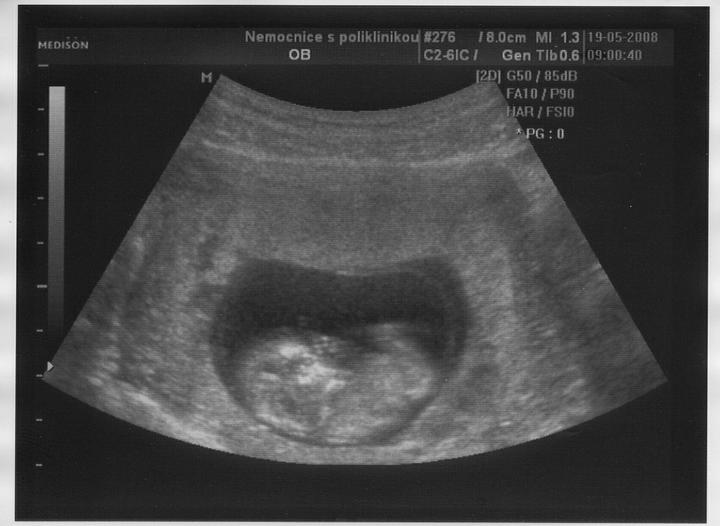

Doktor mi začátkem listopadu 2007 vysadil HA z důvodu zdravotních potíží,dávali jsme si tedy pozor a čekali,zda potíže ustoupí,ale 31.prosince 2007 mi manža řekl,že by chtěl miminko,byla jsem z jeho návrhu vykulená,ale byla to překrásná představa a tak jsem souhlasila..Od 8.ledna 2008 jsme se tedy začali snažit o miminko,začala jsem pít kontryhel a zobat Calibrum babyplan,aby mému tělu nic nechybělo 🙂 Nechávali jsme tomu volný průběh,ani jeden z nás na to nijak nepospíchal,nevím,proč jsem si říkala : Do roka se to snad povede 😀 A 29.3.2008 jsem měla pozitivní testík,sama jsem nechápala,jak brzy se to povedlo 🙂 Byla jsem neskutečně šťastná a stále jsem 🙂 Termín porodu dle MS 5.12.2008 a dle utz ve 12.tt 30.11.2008 Už od začátku jsem tušila,že čekám kluka a tak hned z první kontroly v 5.tt jsem si koupila modré bačkůrky pro štěstí,které se mnou chodili na každou kontrolu 🙂 Od 15.tt mi začalo celkem hodně tvrdnout břicho a chvilkama to bylo velice nepříjemné,na další kontrole,to jsem byla 18+4 , jsem to doktorovi řekla,ten mi pověděl,že se mu to vůbec nelíbí a tak mě poslal na utz,na utz jsem čekala 2 hodiny a můžu říct,že to byli nejhorší 2 hodiny v mém životě,tolik jsem se o miminko bála,ten strach,že něco není v pořádku byl opravdu k nevydržení..Přišla na mě řada a tak jsem tedy šla do kabinky a následně na lehátko na utz,pan doktor konstatoval,že všechno vypadá v pořádku a že se nemám bát,předepsal mi magnezium a že by to mělo pomoct,navíc koukám na ten utz a povídám panu doktorovi,to co tam vidím jsou kouličky? 😀 A on že jistě,že si myslel,že už to dávno vim,když se tak krásně ukazuje 😀 ,můj doktor mi řekl,že zřejmě porodím předčasně,což mě celkem vyvedlo z míry..Ale jsem optimisticky naladěnej človíček a tak jsem Honzíkovi vysvětlovala,že v bříšku musí ještě zůstat..Ve 20.tt jsem šla na velkej UTZ,kde mi opravdu řekli,že Honzík je zdravej a opět Honzík ukázal,že je 100% chlapeček 😀 Ve 26.tt jsme jeli na 4D utz do Liberce,tam se Honzík ukázal zas,no za celé těhu se nestalo,že by se na utz neukázal aa neroztáhl nožičky,máme malýho exibouše 😀 Ve 30.tt mě čekal další UTZ,vše v pořádku,Honzík už byl hlavičkou dolů a vážil 1600g ..Ve 35.tt mě doktor opět kvůli tvrdnutí břicha poslal už do ambulance,aby se o mě starali už tam.. Ten den jsem strávila v nemocnici 7hodin,fakt děsný !!! 2 hodiny čekání u mého doktora,ten mě tedy poslal už do nemocnice,takže jsem musela na UTZ,tam jsem čekala 2 hodiny,pak na natáčky,tam jsem čekala hodinu a pak na ambulanci a tak jsem čekala zas dvě hodiny ☹ Na UTZ ve 36.tt měl Honzík už 2600g ..